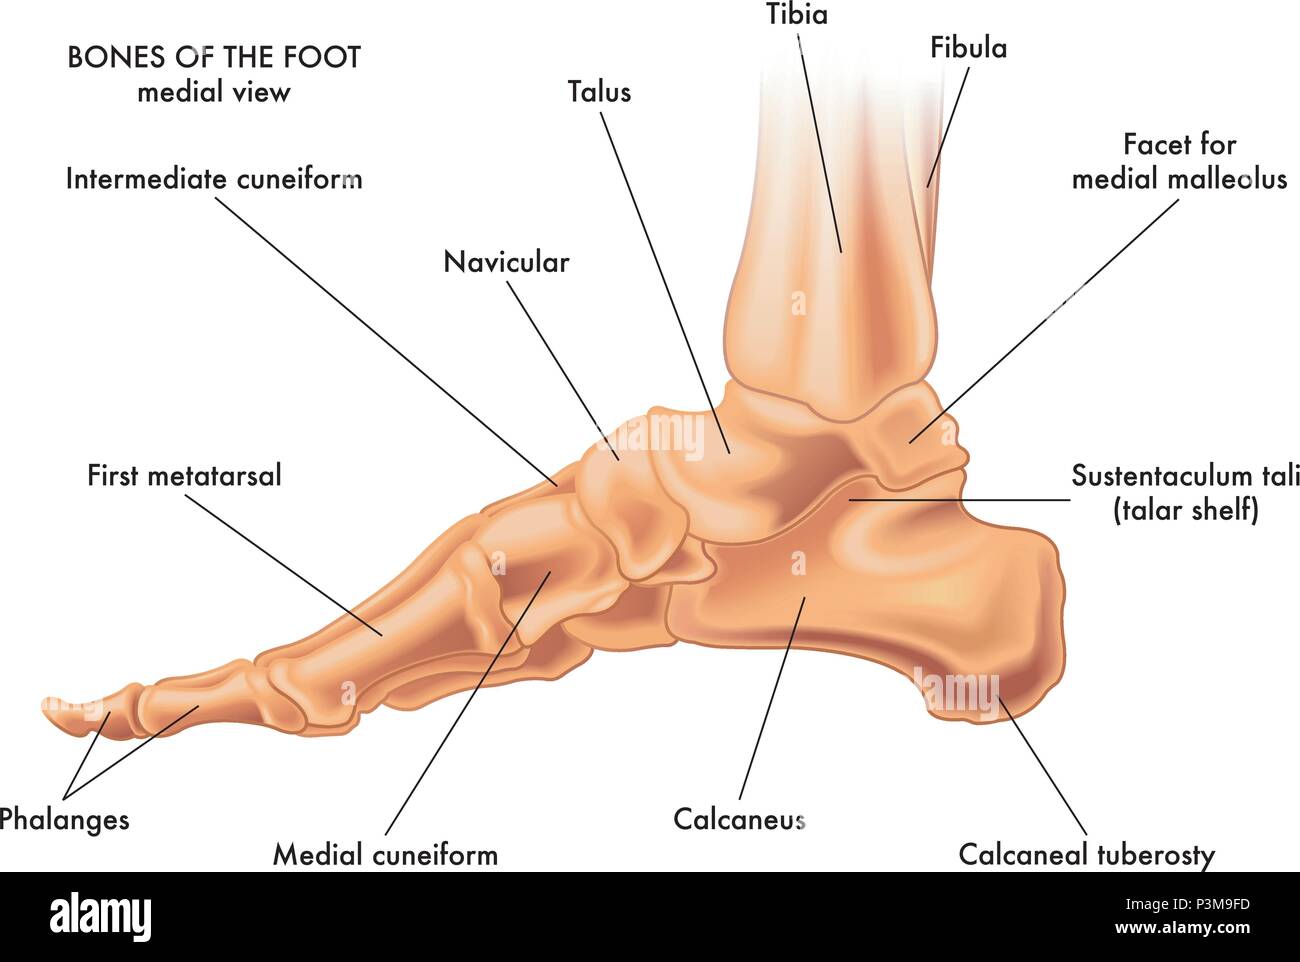

RF2R3WKY1–Illustration médicale des principales parties des os du pied en vue latérale, avec annotations.